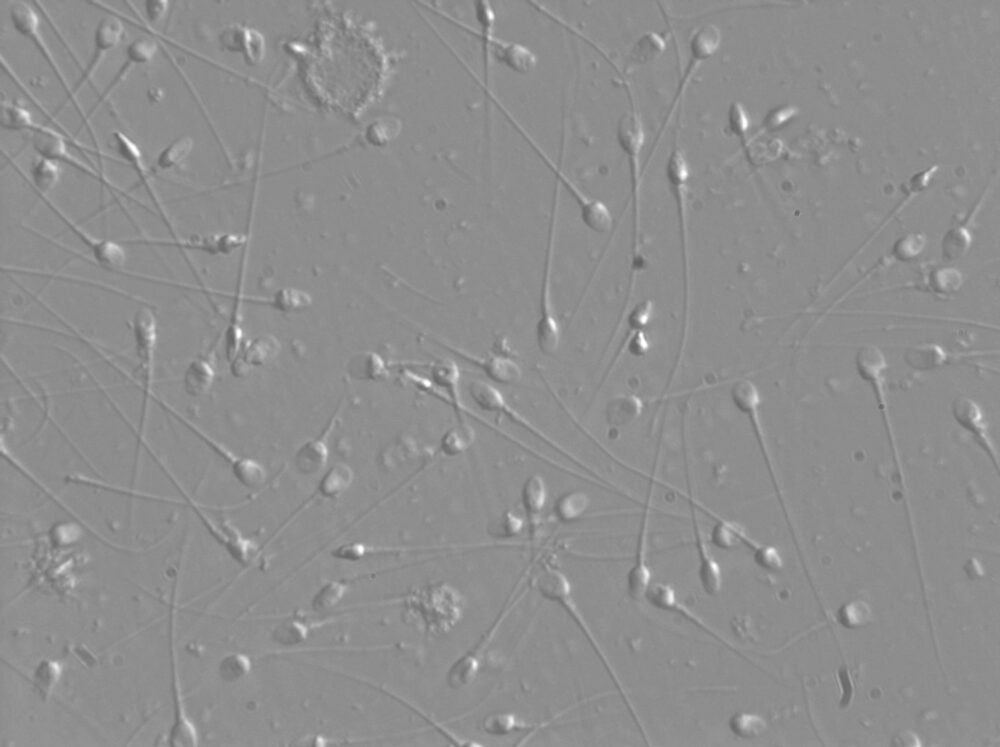

IMSI is a technique that helps IVF embryologists select the best sperm as a high proportion of sperm even in healthy men have some abnormalities.

To assist this process an emerging treatment is Intra-cytoplasmic Morphologically Selected Sperm Injection (IMSI) where the sperm is viewed at very high magnification, using an inverted microscope. This enables the embryologist to look inside the head of the sperm to identify the healthiest looking sperm for injecting in to an egg using ICSI.